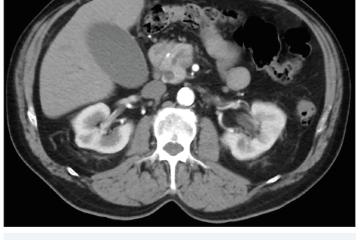

Několik studií se zabývalo AI asistovanou CT detekcí karcinomu pankreatu s AUC 0,79–0,99 %,6–8 tedy přesností porovnatelnou s přesností práce zkušeného radiologa. Stran časné detekce proběhla studie posuzující přesnost AI modelu v detekci karcinomu pankreatu v období 3–36 měsíců před prvními projevy onemocnění. Zařazeno bylo 155 pacientů s karcinomem pankreatu a 265 zdravých kontrol. AI model zde dosáhl AUC 0,98, což výrazně předčilo radiology, kteří při popisování stejných případů dosáhli AUC 0,66.9 Studie využívající DL model pro rozlišení zdravé slinivky od nálezu pankreatických neoplazií, tedy karcinomu pankreatu, intraduktální papilární mucinózní neoplazie (IPMN), serózních a mucinózních cystických neoplazií a solidní pseudopapilární neoplazie, byla prezentována s AUC 0,91, tedy opět odpovídající přesnosti popisu radiologa.10 Pro další vývoj a možné klinické využití bude potřeba přístupu k rozsáhlému archivu CT snímků karcinomu pankreatu, aby se ML modely mohly zdokonalovat. Další studie se věnovaly AI asistované diferenciální diagnostice. Ta bývá u lézí pankreatu velmi obtížná a pokrok v této problematice je tak velmi přínosný. Mezi nejzajímavější patří studie zabývající se rozlišením serózních a mucinózních cystadenomů s AUC 0,932.11 Další studie zkoumala úspěšnost rozlišení karcinomu pankreatu od zbytnění pankreatu při určitých formách chronické pankreatitidy (MFP – mass forming pancreatitis) s AUC 0,866.12 V další studii byla AI využita k rozlišení fokální autoimunitní pankreatitidy od karcinomu pankreatu s AUC 0,97.13 V rámci MR proběhlo několik studií, které se zaměřily na AI asistované zachycení a klasifikaci pankreatického karcinomu či IPMN. Studie klasifikující IPMN pomocí konvoluční neuronové sítě (CNN – convolutional neural network) byla schopna rozlišit dysplazii vysokého stupně od přítomnosti karcinomu se senzitivitou 76 %, specificitou 78 % a AUC 0,78.14 Další studie porovnávala AI modely CT a MR v predikci maligního IPMN. Výsledky ukázaly, že MR model s AUC 0,94 byl přesnější než CT model s AUC 0,864.15 S využitím PET/CT byl prozkoumán AI model rozlišující od sebe akutní pankreatitidu a karcinom pankreatu s AUC 0,9668.16 Výsledky AI v oblastech zobrazovacích metod jsou tak slibné. Dosahují minimálně přesnosti srovnatelné s radiologem a zejména v problematice časných karcinomů pankreatu člověka svojí přesností převyšují (obr. 1–5).

EUS umožňuje přesné vyšetření pankreatu. Lze také identifikovat a vyšetřit regionální lymfatické uzliny a vztah pankreatických lézí k okolním cévním strukturám. EUS může také sloužit jako navigace k odběru bioptického materiálu k cytologickému a histologickému vyšetření.21 AI je zde využívána k potvrzení malignity v IPMN. Kuwahara a kol. dosáhli s využitím 3 970 snímků a CNN algoritmu velké úspěšnosti v diferenciaci benigní a maligní IPMN s AUC 0,98.22 Řada studií se již zabývala AI asistovaným rozlišením chronické pankreatitidy a karcinomu pankreatu s AUC 0,940–0,986.23,24 Velká studie obsahující 1 174 461 snímků z celkem 583 případů hodnotící rozlišení autoimunitní pankreatitidy, karcinomu pankreatu, chronické pankreatitidy a normálního pankreatu dosáhla pro karcinom pankreatu AUC 0,97625 (obr. 6–9).